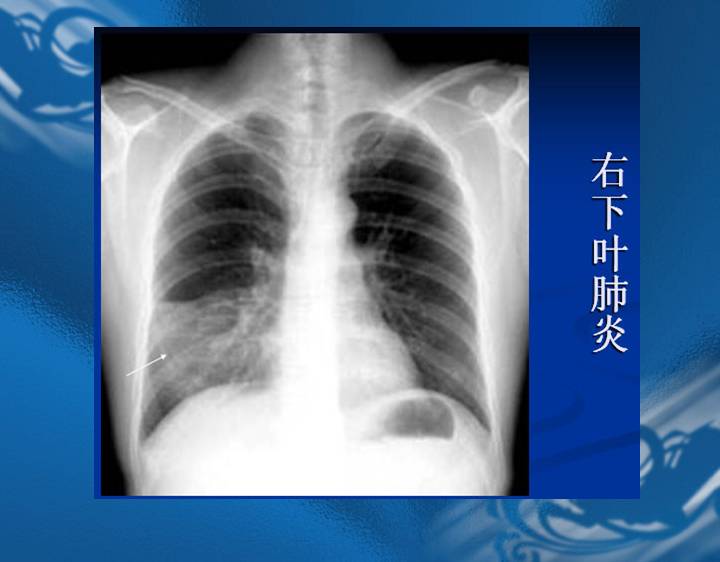

执业医师资格考试“实践技能”影像学辅导资料